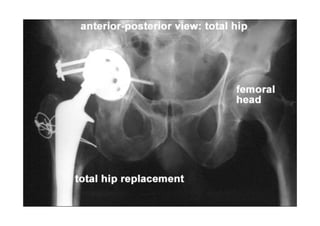

RADIOLOGIA DO

TRAUMA DO ESQUELETO

Referência: http://www.accessexcellence.org/RC/VL/